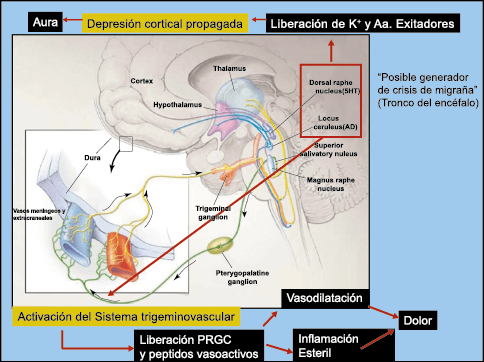

El aura de la migraña, al menos en su sentido clásico, tiene relación con la depresión cortical que se propaga por la corteza cerebral y participa como un actor paralelo cuando se producen las crisis. (Figura 2)

En la primera fase (figura 3), premonitoria, que precede a la cefalea, los sistemas del tronco encefálico y diencefálico modulan las señales aferentes, la fotofobia a la luz o la fonofobia al sonido, comienzan a disfuncionalizarse y eventualmente a evolucionar a la fase de dolor y con el tiempo a la fase de resolución o posdrómica. Aproximadamente en un tercio de los pacientes con migraña, sus ataques están asociados con déficits neurológicos, que incluyen perturbaciones corticales, denominadas colectivamente aura de migraña(3).

Se cree que una onda transitoria de despolarización neuronal de la corteza (Figura 9), la depresión de propagación cortical (CSD), es el mecanismo cerebral fisiopatológico subyacente al fenómeno clínico del aura de la migraña. Leão(21) estableció un mecanismo subyacente hipotético. Luego de haber estimulado eléctricamente la corteza de conejo y encontrar una depresión EEG que se propagaba a una velocidad similar de 3 mm/min centrífugamente desde el sitio de estimulación sugirió que podría ser la base del aura migrañosa. Esta hipótesis está fundamentada en la correlación entre las características neurofisiológicas de una CSD, su propagación retinotópica en la corteza visual y las características y dinámicas de los déficits visuales(14, 15) y en las observaciones indirectas derivadas de los estudios de imágenes que respaldan aún más este concepto(16) Sin embargo, sobre la base de la comprensión actual de la migraña, es poco probable que la CSD esté involucrada en el inicio del síndrome completo de la migraña(17).